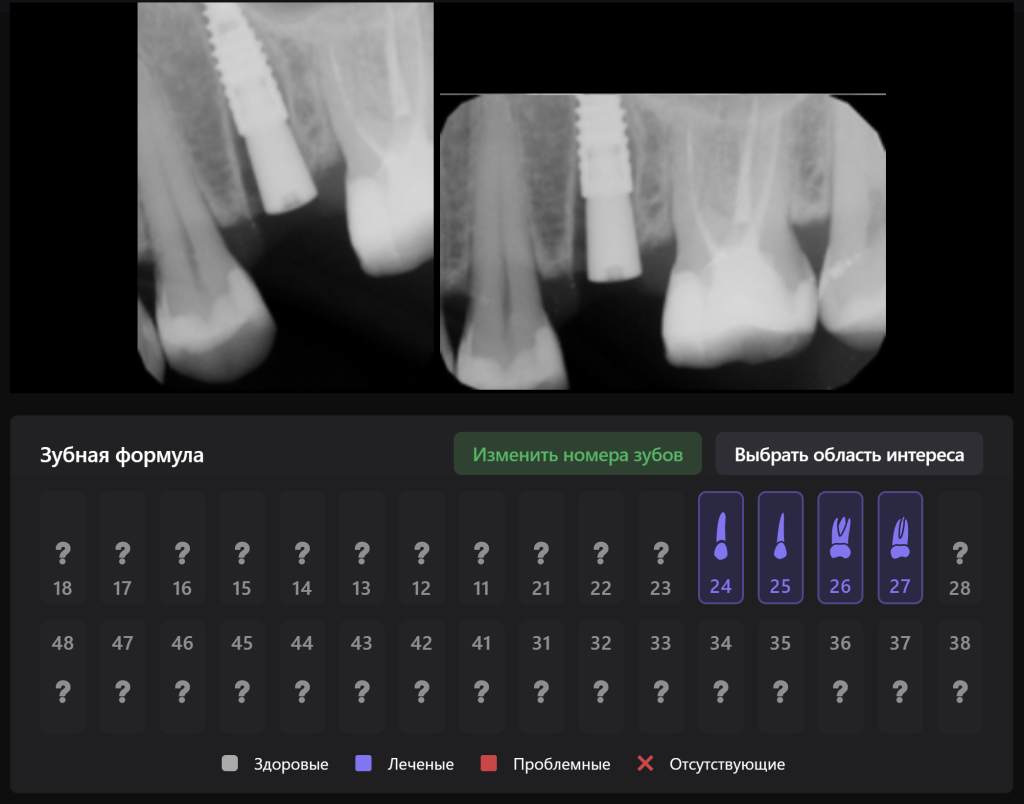

The planning of immediate implant placement using Diagnocat AI has many advantages for both the doctor and the patient. Let’s consider them using a clinical case example, in which the removal of tooth 25 (Universal 13) and subsequent implant placement were planned

The patient came with complaints that his dental crown on tooth 25 (Universal 13) fell out

In order to predict the prognosis of the tooth, data from the Diagnocat radiological report and visualization capabilities of the 3D-Viewer tool were utilized, in addition to a clinical examination